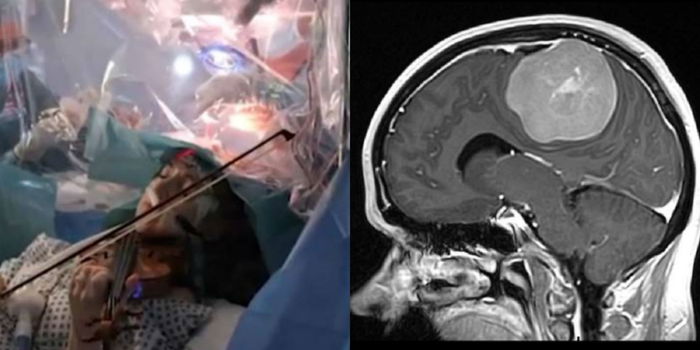

Wanita berkenaan yang juga merupakan bekas perunding pengurusan dari Isle of Weight itu memainkan biola semasa pembedahan bagi mengeluarkan ketumbuhan di bahagian kanan lobus frontal otaknya.

Ia berhampiran dengan bahagian untuk mengawal pergerakan di tangan kirinya.

Bagi mengelakkan Turner hilang upaya untuk bermain biola, Perunding Pakar Neuro di Hopital King’s College, Profesor Keyoumars Ashkan, membuat perancangan dengan melakukan lakaran membuka tengkorak kepala Turner

Dalam masa yang sama, pembedahan itu menyaksikan kejayaan pakar perubatan mengeluarkan 90% ketumbuhan termasuk bahagian yag disyaki berlakunya pergerakan ketumbuhan yang aktif.